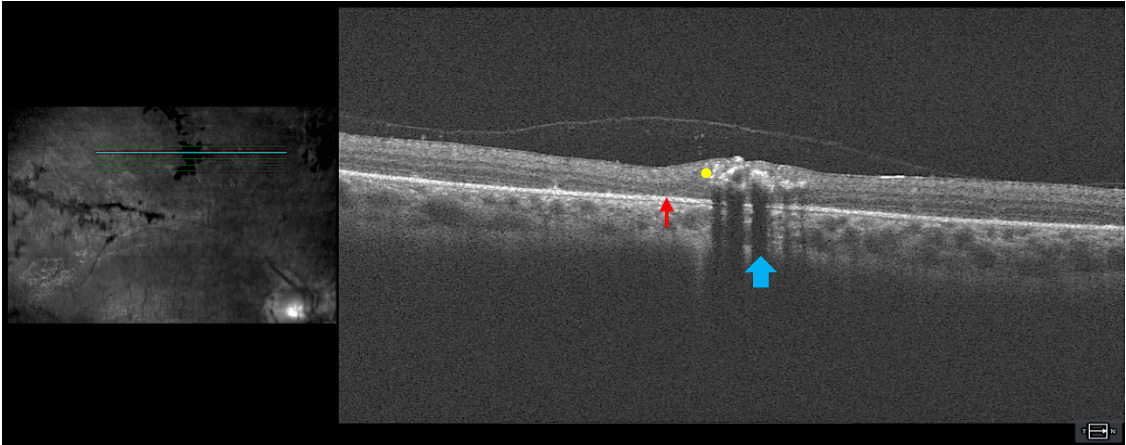

Optical coherence tomography: Figure 3 includes a high-definition 5-line raster through an area of perivenular pigment clumping and atrophy. Hyperreflectivity from retinal pigment (yellow dot) can be seen in the neurosensory retina with shadowing of deeper retinal layers (blue arrow). An epiretinal membrane can be visualized, which correlated with the enhanced retinal sheen seen funduscopically. Increased retina thickness around the abnormality, as compared with the thickness of the adjacent normal retina, was evident. The sub–retinal pigmented epithelium space in the areas of the scan that are not in the shadowed zone appear unremarkable. There were subtle areas of outer retinal layer thinning adjacent to the abnormal pigment (red arrow). The optical coherence tomography imaging indicated that although the retinal pigmentation accumulation was in the inner retinal layers because of the anatomical location of the branches of the central retinal vein, retinal atrophy can be visualized in the adjacent outer retina. This gives insight into presentation of chorioretinal atrophy in the perivenular region.